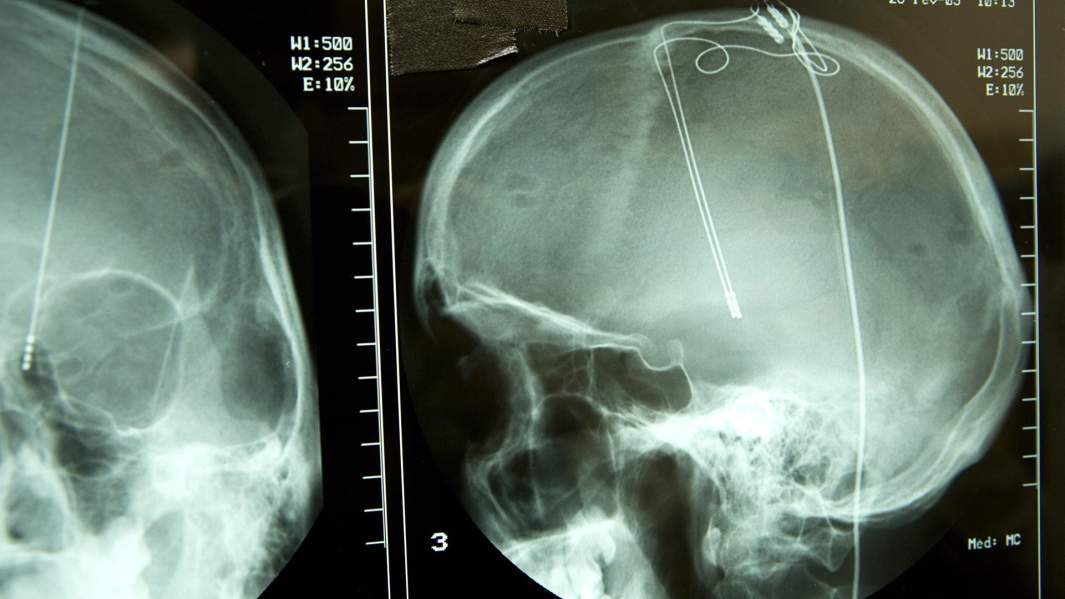

Российские программисты совместно с учеными группы функциональной нейрохирургии Оксфордского университета приступили к работе по устранению уязвимостей, найденных в работе нейроимплантов. Современные методы лечения многих заболеваний предполагают установку в мозг электродов, подключенных к генератору импульсов. Настройки такого устройства меняет врач с помощью специальных программ. А значит, воздействовать на него могут и злоумышленники. Подобная вероятность возникает и при имплантированном кардиостимуляторе. Ученые и эксперты по информационной безопасности рассказали «Известиям» о том, какие последствия могут иметь такие взломы и как их предотвратить.

Нейроимплант состоит из электрода и генератора импульсов. Электрод, ведущий в определенную зону мозга человека, прикреплен к небольшой «шайбе» диаметром примерно 4 см, которая внедрена под кожу на голове. В «шайбе» размещена батарея, Bluetooth-модуль и генератор импульсов.

Воздействие на генератор импульсов регулируется с помощью программатора, который позволяет менять настройки импланта и следить за состоянием пациента. В этой роли обычно выступает планшет или смартфон со специальным программным обеспечением.

Передача данных между имплантом и цифровым устройством осуществляется по Bluetooth-каналу, подключиться к которому для злоумышленника не представляет труда. А в будущем процедура коррекции настроек устройств и вовсе будет осуществляться через Сеть, что гораздо удобнее — пациенту не придется каждый раз приезжать к врачу на прием лично, чтобы скорректировать работу импланта. Однако при этом может возникнуть еще большая проблема по обеспечению безопасности соединения.